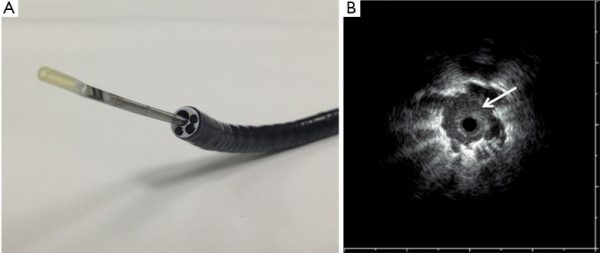

Για πρώτη φορά στη Βόρεια Ελλάδα ήρθε και εφαρμόζεται ο ενδοβρογχικός υπέρηχος RADIAL–ENDOBRONCHIΑL ULTRASOUND.

Ενδοβρογχικός υπέρηχος CONVEX–PROBE

Μια ακόμα πρωτοπόρα τεχνική για τη διάγνωση και σταδιοποίηση του καρκίνου του πνεύμονα είναι ο ενδοβρογχικός υπέρηχος CONVEX–PROBE.